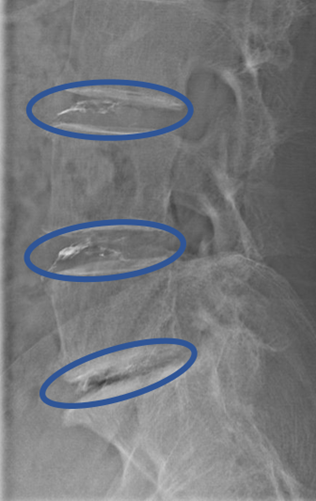

患者様と相談の元、 L3/4,4/5,5/s にセルゲル法を施行

治療は簑輪医師が行いました。

DiscoGelを入れた後の画像になります。

治療は 30分程度で終了

回復室で休憩後、歩いて帰院されました。